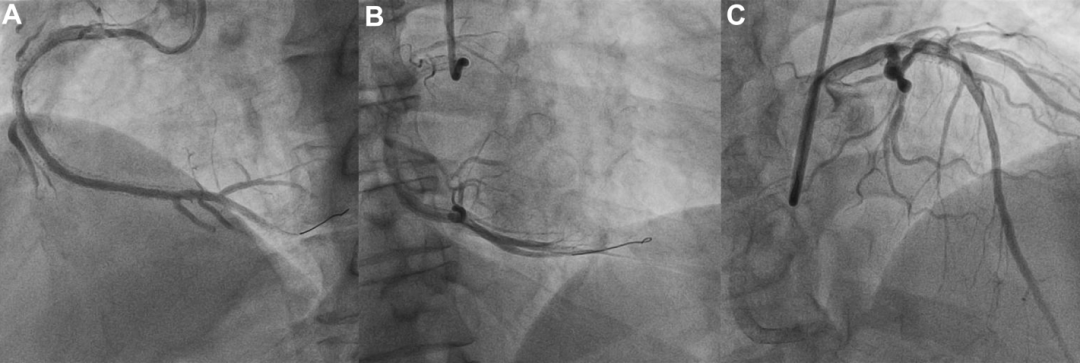

冠状动脉造影结果显示,LAD和回旋支(LCX)无明显狭窄;RCA中段存在弥漫性支架内再狭窄,远端呈CTO改变;LCX向远端RCA提供了良好的心外膜侧支循环(图1)。

图1 冠状动脉造影结果

冠脉造影显示(A和B)LAD、LCX无明显狭窄,LCX远端有心外膜侧支血管供应RCA远端;(C)LCX远端有发育良好的心外膜侧支血管供应RCA远端;(D)RCA中远端弥漫性支架内再狭窄,且RCA远端为CTO。